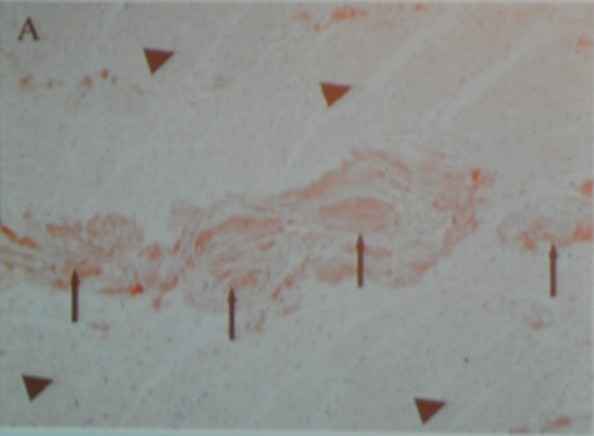

3、电子显微镜下的心肌细胞和细胞外组织

除了定性检测,我们还需要做一些更加精确的定量检测。这是一个电子显微镜下的心肌细胞和细胞外组织。心肌细胞外组织是非常致密且有规则的结构,心肌细胞素会从中通过。但是当患者存在肥厚性心肌病或者高血压心肌病时,纤维组织就在心肌细胞外的组织沉着,导致心肌肥厚和舒张功能不全。这是定性检查所不能做到的。

4、心肌细胞外组织容量的定量检测与心肌纤维化的关系

这是最近非常新的一种检测手段,这使得磁共振对心肌的认知又到了一个新的高度。高血压心肌病、糖尿病心肌病患者的心肌组织都存在不同程度的纤维化,这有可能为今后的治疗提供一个方向。